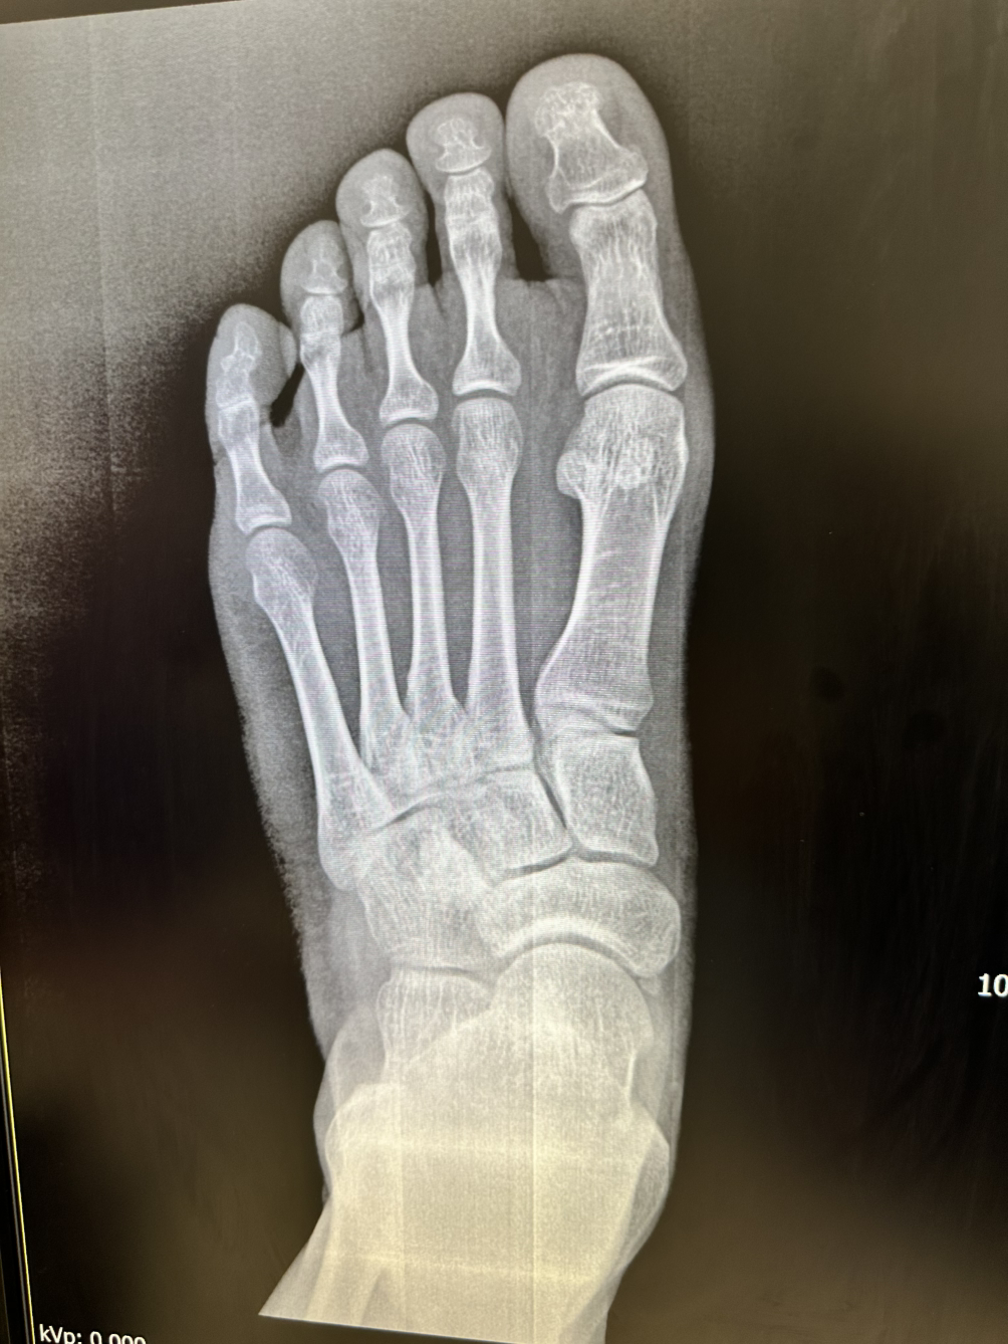

3월 결산에 요즘 산책하는 게임을 하느라 많이 걷는다고 언급했는데, 어느 날 저녁 2만보를 걸었더니 발바닥이 아프기 시작했다. 통증이 심상치 않아 집 앞 정형외과에 갔더니 발이 평발이고 '부주상골'이라는 없어도 되는 작은 뼈가 하나 있어 구조적으로 많이 걸을 수 없는 발이라는 이야기를 들었다. TV 건강 프로그램에 종종 출연하시는 선생님이라 설명을 어찌나 찰떡같이 해주시던지...

"그러니까 환자분 왼발 발가락 받쳐주는 다섯 형제 뼈가 있는데, 가장 힘세고 돈 많은 엄지 뼈는 맨날 놀고먹느라 나머지 뼈들이 뼈 빠지게 일해서 걷고 있는 겁니다." 뼈가 뼈 빠지게 일한다니 선생님 표현력은 처방 안 해주시나요...

엄지쪽 뼈가 저렇게 휘어있으면 안 된다고…

여하튼 그래서 달리기나 등산을 하면 발이 쉽게 피로해지고, 더 무리하면 이렇게 염증이 생길 수도 있으니 운동을 하려면 수영을 하거나 자전거를 타라고 하신다. 말 잘 듣는 나는 따릉이 6개월 정기권을 결제했다. 내가 하는 산책 게임은 자전거를 느리게 (시속 20km/h 미만) 타도 걷는 것과 비슷한 효과가 있으니 쉬엄쉬엄 매일 밤 1-2시간 정도 따릉이를 타러 나간다. 집이 서울 동쪽 끝이라 한강을 타고 동쪽으로 달리다 보면 남양주/팔당으로 가게 된다. 밤 11시 12시의 한강 자전거길은 사람이 하나도 없어서 정말 고요하다. 처음엔 오디오북이라도 들으며 달릴까 했는데, 그 고요함도 나쁘지 않은 것 같아서 음악도 오디오북도 없이 달리고 온다.